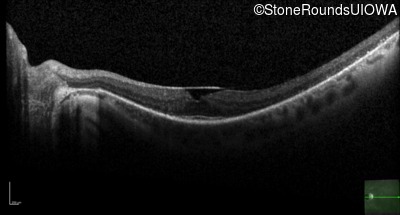

Optical Coherence Tomography - Right - 20/25 -2 sc

Exemplar / OCT Stack

OCT Stack